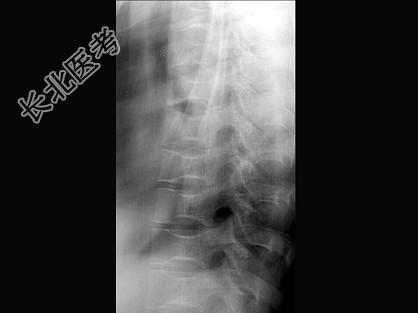

- 单项选择题女,24岁, 反复发作的骨骼肌肉痛,结合图像, 最可能的诊断是 ( )

A、镰状细胞贫血

B、地中海贫血

C、骨梅毒

D、白血病

E、椎间盘突出